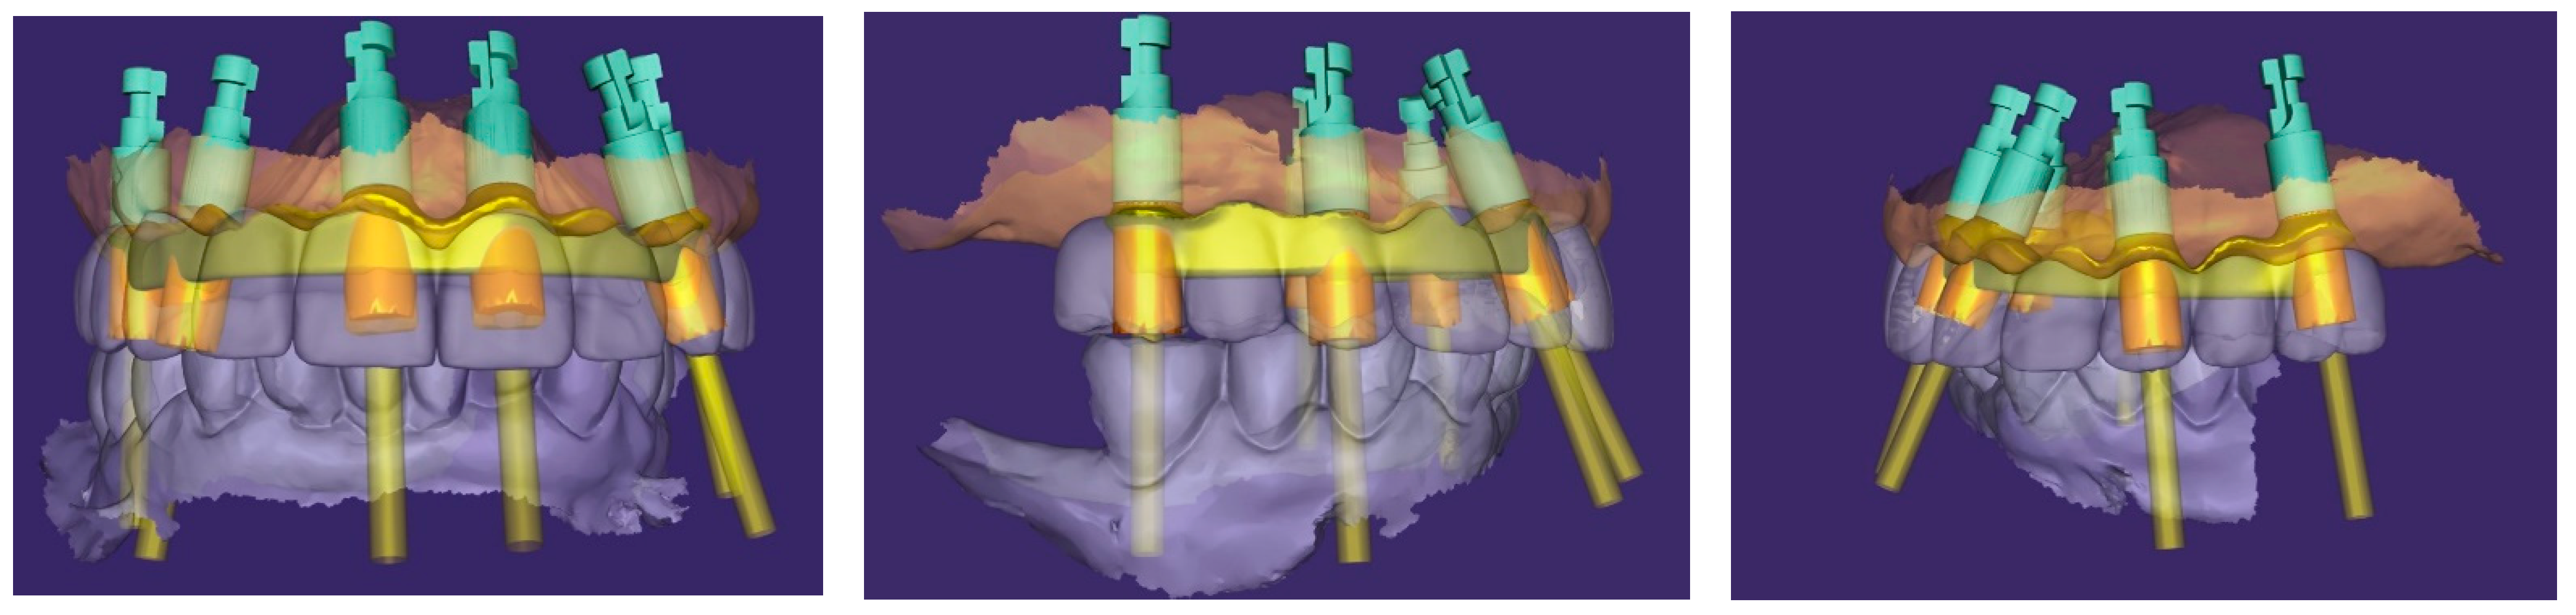

An additional intraoral registration was performed at the level of the multi-unit abutments (MUAs) using scan flags (Shining 3D Tech Co., Ltd., Hangzhou, China) in combination with photogrammetry (Figure 14). This workflow allows the three-dimensional implant positions to be recorded with high trueness and precision, thereby reducing the risk of cumulative errors inherent to conventional intraoral scanner (IOS) stitching, as highlighted in recent in vivo and in vitro studies [2,21].

The Shining3D scan flags are designed to capture IOS and photogrammetry data simultaneously within a controlled and stable scanning pathway. Their integrated fiducial markers enable the software to perform a dual alignment process, cross-referencing implant positions between photogrammetry data, IOS meshes, and the scanned soft tissues. The resulting dataset provides a unified and highly accurate digital model of the clinical situation, which can efficiently be exported to the dental laboratory for prosthetic planning and design [3].

In parallel, the provisional restoration was scanned, and the datasets were merged with CBCT in Exocad software. This workflow allowed for the faithful transfer of the verified occlusal relationships, phonetics, and soft tissue contours which were accepted by the patient during the provisional phase and thus served as a reliable reference into the definitive design.

Based on this integration, a screw-retained titanium bar was digitally designed (Figure 15) and subsequently milled. The passivity of the framework was clinically verified with a PMMA try-in prosthesis and radiographic evaluation.

Figure 15. Digital project of the maxillary arch in Exocad. The images show the planned implant positions with their axes, corresponding multi-unit abutments, and the designed metal framework (yellow overlay) for full-arch prosthetic restoration (front, right and left side view).